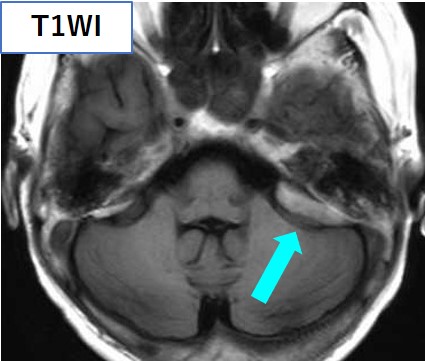

頭部CT・MRIにて、大脳鎌に沿った腫瘤を認め、左小脳橋角部にも腫瘤を認める。いずれもT1強調像で高信号、T2強調像で低信号を呈している。

頭部MRI